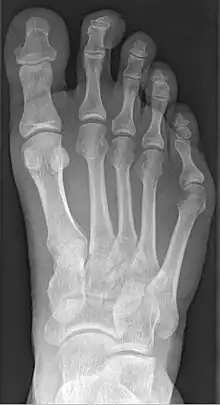

Radio de pied atteint de la bunionette

La bunionette est facilement diagnostiquée, car la saillie est apparente. Des radiographies peuvent être prescrites afin d'aider le chirurgien à déterminer l'ampleur de la déformation.